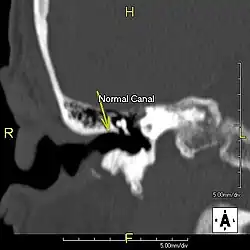

Exostose du surfeur

L'exostose du surfeur ou oreille de surfeur est une exostose, c'est-à-dire une croissance osseuse anormale, qui pousse vers l'intérieur du conduit auditif[1]. L'os entourant le conduit auditif réagit à l'agression thermique et mécanique de l'eau froide et de ses turbulences, par une nouvelle croissance osseuse qui a pour effet de resserrer le conduit auditif.